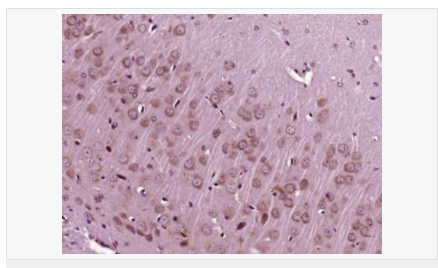

| 产品应用 | WB=1:500-2000 ELISA=1:5000-10000 IP=1:20-100 IHC-P=1:100-500 IHC-F=1:100-500 IF=1:100-500 (石蜡切片需做抗原修复) not yet tested in other applications. optimal dilutions/concentrations should be determined by the end user. |

| 免 疫 原 | KLH conjugated synthetic peptide derived from human IGF-1:49-100/195 |